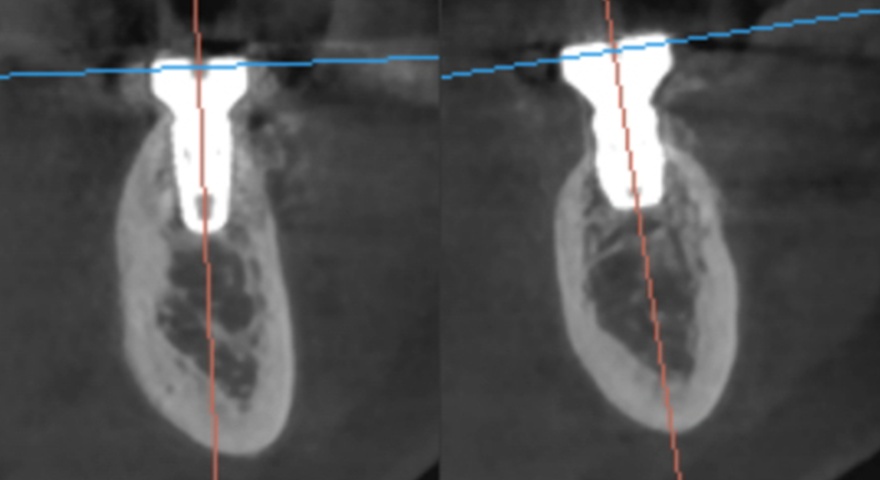

Гістологічні зрізи трьох отриманих імплантатів — демонструють регенерацію букальної кістки через шість місяців після імплантації. Чорна горизонтальна лінія позначає найбільш корональну точку контакту букальної кістки з імплантатом, а червона лінія вказує на початковий рівень букальної дегісценції під час встановлення імплантата, що дозволяє оцінити утворення нової кістки.

Рис. 3. Гістологічні зрізи трьох отриманих імплантатів:

(A) зразок 1 (верхня щелепа),

(B) зразок 2 (нижня щелепа),

(C) зразок 3 (нижня щелепа),